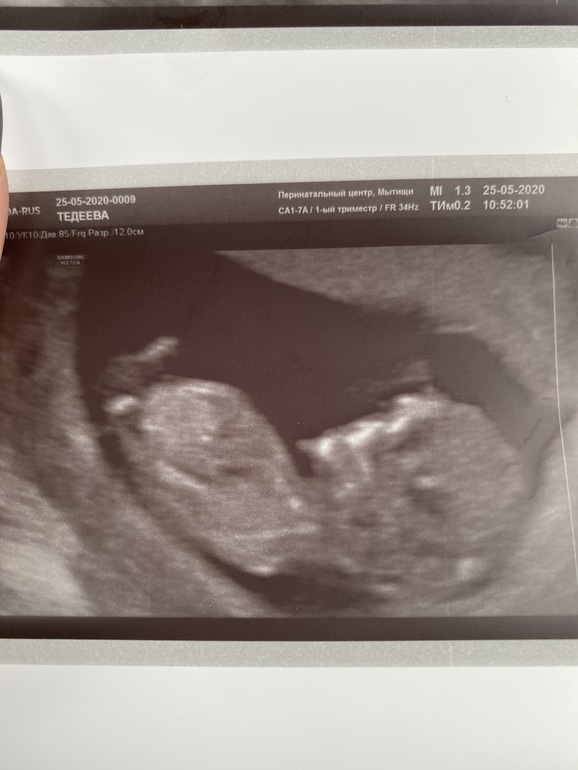

Пол малыша

Девочка))

Где это видно? Я не верю в такое счастье)

Ну вот на верхней фотке по половому бугорку)

мне тоже кажется, что девулечка!

По лицу предположу, девочка😜

Не 100% но мне похоже девочка

Пусть будет девочка)